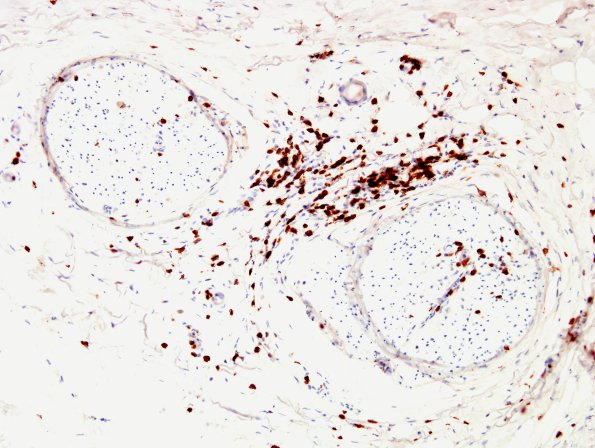

2C2 GBS (Case 2) CD3 3

Several magnifications of endoneurial and perineurial T cell inflammation (CD3 IHC)